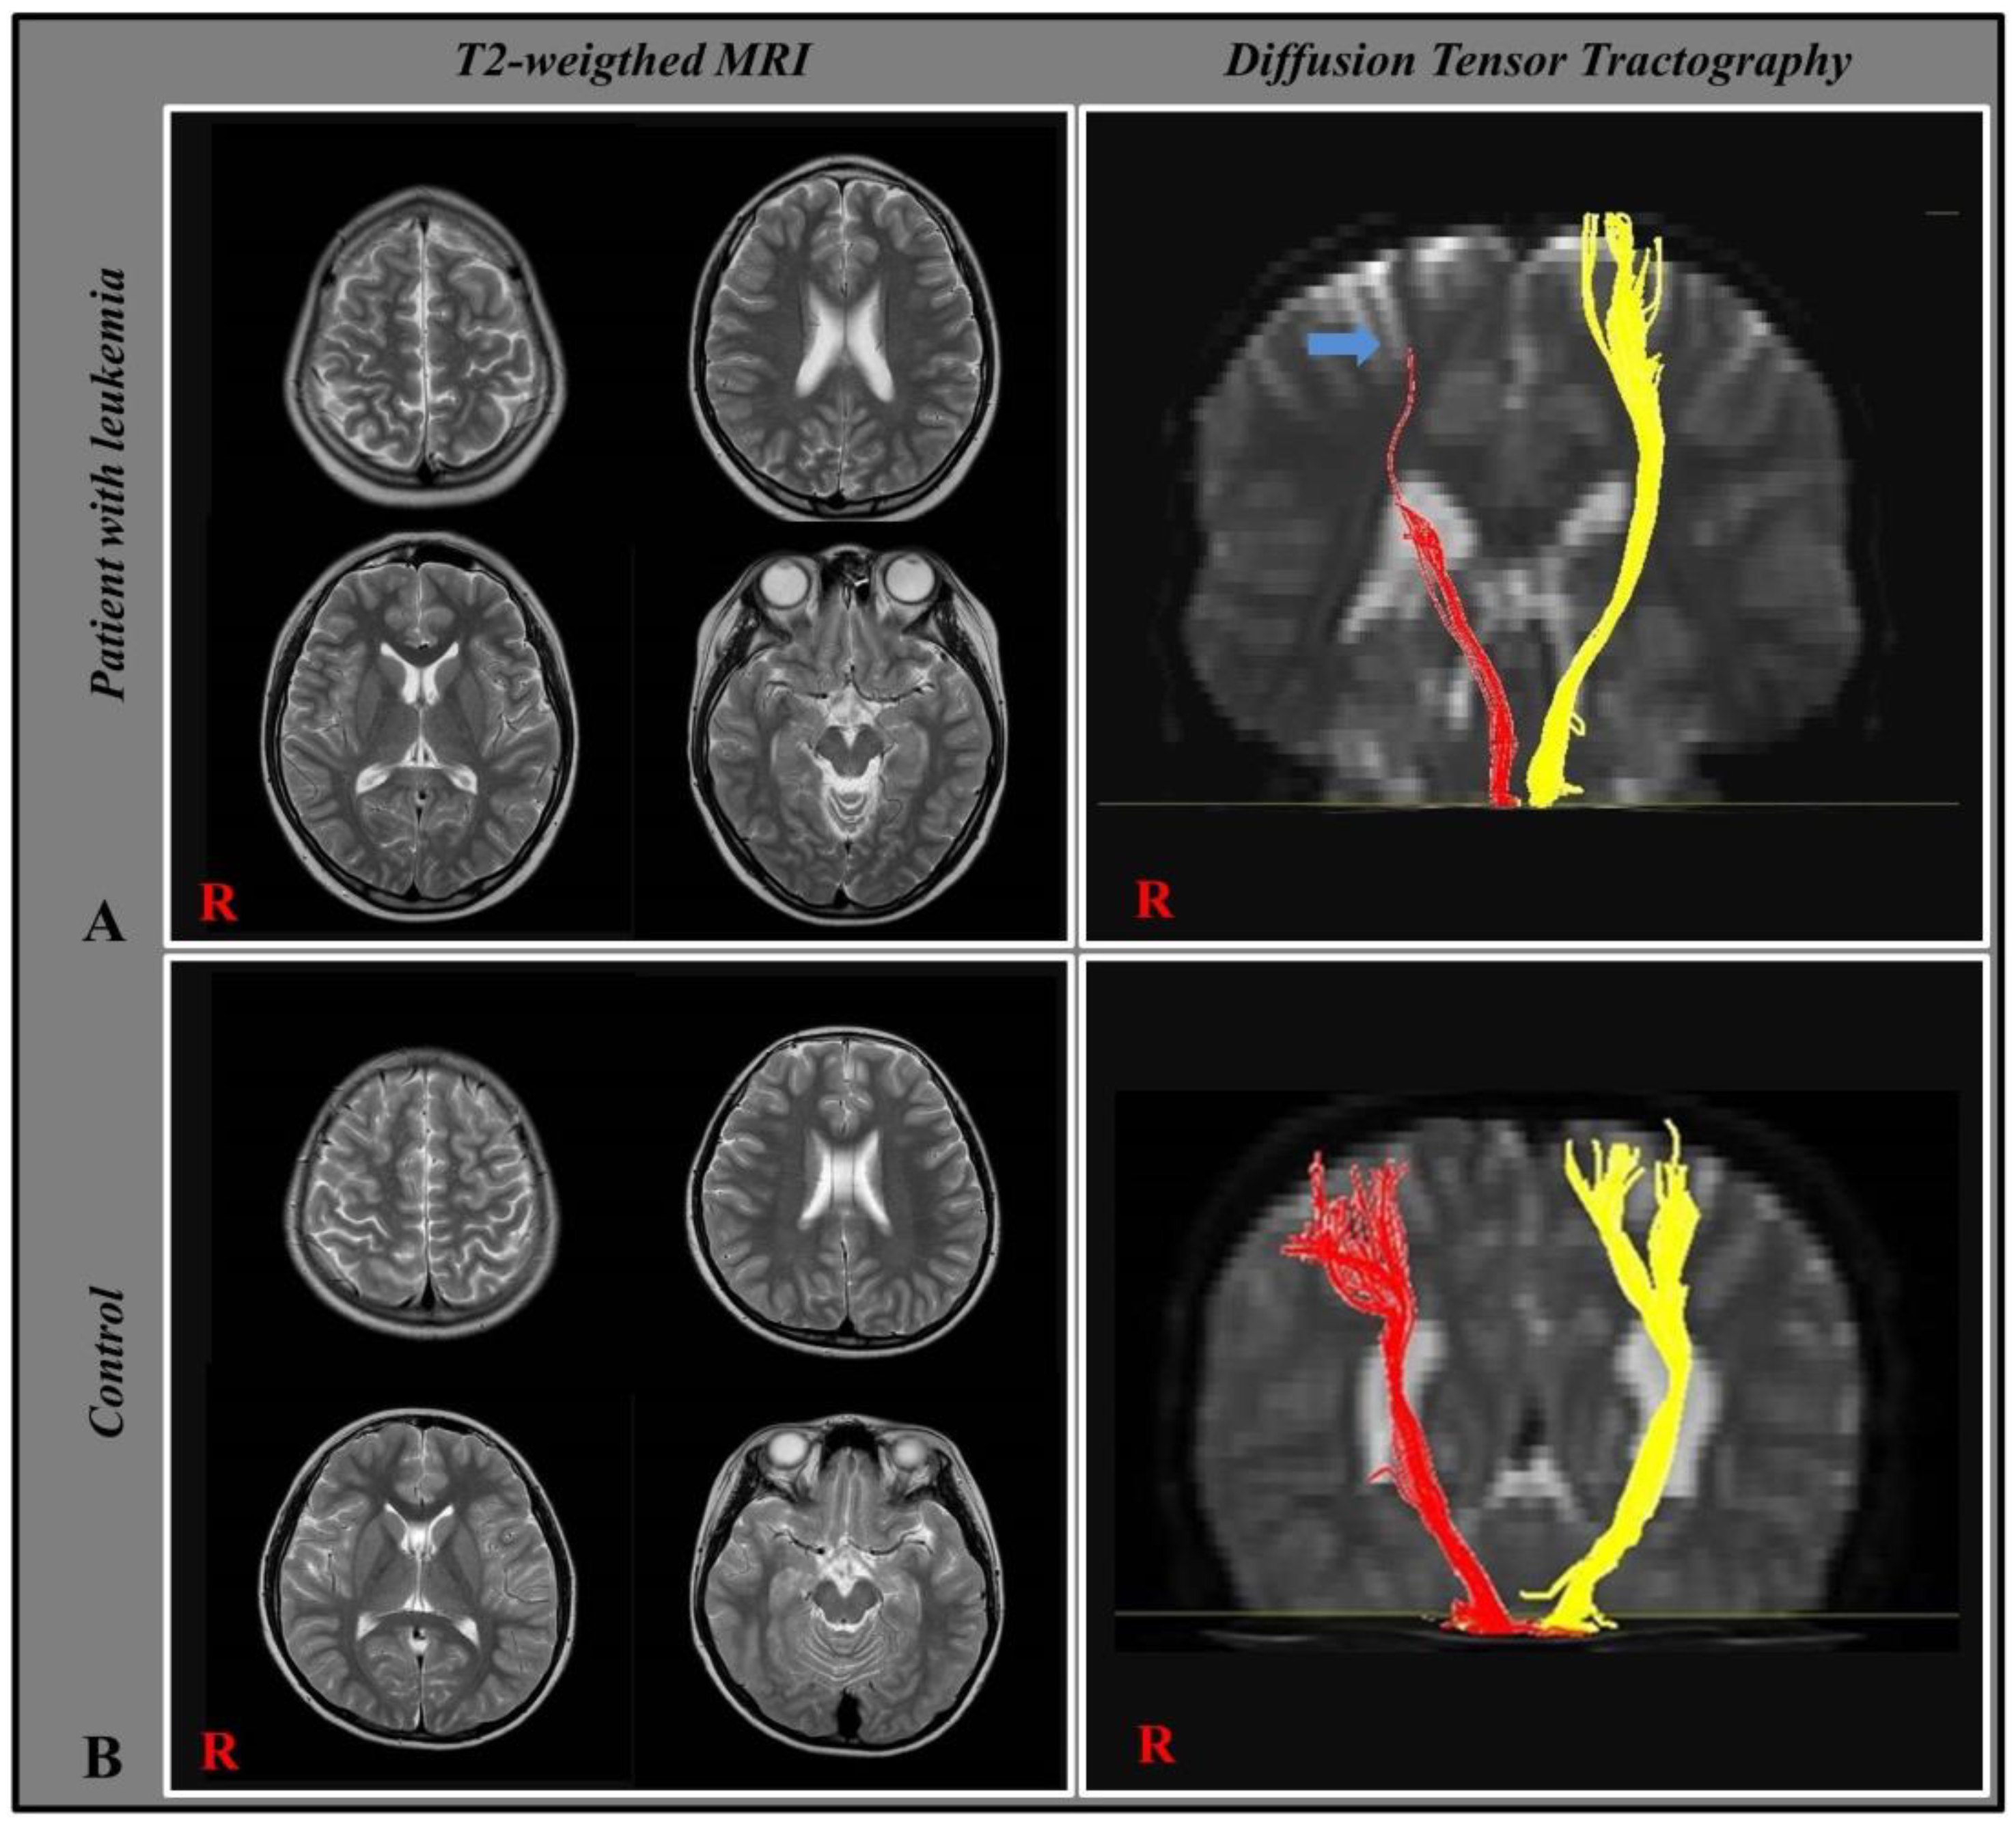

3.2. Diffusion Tensor Tractography

- Lee, J.M.; Kim, J.B.; Byun, D.H.; Son, S.M. Disruption of the corticospinal tract in patients with acute lymphoblastic leukemia: A case series. Children 2022, 9, 1223. [Google Scholar] [CrossRef]

| CST | Patients Group (n = 19) | Control Group (n = 20) | p-Value |

|---|---|---|---|

| FA | |||

| Affected side | 0.309 ± 0.052 | 0.579 ± 0.05 | 0.001 * |

| Unaffected side | 0.528 ± 0.053 | 0.579 ± 0.05 | 0.005 * |

| p-value | 0.003 * | - | - |

| FV | |||

| Affected side | 289.8 ± 100 | 1081.8 ± 171 | 0.001 * |

| Unaffected side | 869.6 ± 131 | 1081.8 ± 171 | 0.002 * |

| p-value | 0.005 * | - | - |